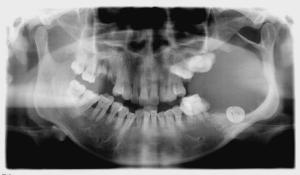

典型X線表現:早期呈蜂房狀,以後形成多房性囊腫樣陰影,單房較少。周圍囊壁邊緣常不齊整,呈半月形有切跡及有密度增高的骨白線,腫瘤生長可導致牙移位、囊內牙根呈鋸齒狀或截根狀吸收,伴埋伏牙者可表現類似於含牙囊腫的X特點。

各型成釉細胞瘤同樣的X線特徵歸納為以下六點

1)骨質膨隆,以向唇頰側向為甚;

2)骨密質消失,以牙槽側骨消失多見;

3)腫瘤內含牙或不含牙,所含牙可為各發育期的埋伏牙、阻生牙或多生牙;口內牙被腫瘤推移、鬆動或脫落;

4)牙根呈鋸齒狀吸收,腫瘤部分邊緣骨質增生硬化

5)腫瘤可向根與根之間浸潤;

6)腫瘤無鈣化。

根據病史、臨床表現、X線特點,可作出初步診斷。典型成釉細胞瘤的X線表現:早期呈蜂房狀,以後形成多房性囊腫樣陰影,單房比較少。成釉細胞瘤因為多房性及有一定程度的局部侵潤性,故囊壁邊緣常不整齊、呈半月形切跡。在囊內的牙根尖可有不同吸收現象。

X-ray表現